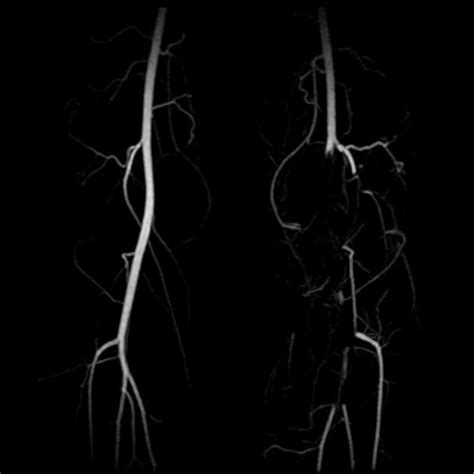

Diagnosing PAES can be a bit of a challenge, guys, because, as we mentioned, the symptoms can mimic other leg problems. But doctors have several tools in their arsenal. The first step is usually a thorough medical history and physical examination . The doctor will ask about your symptoms, when they occur, and your activity levels. They’ll likely check pulses in your feet and legs, both at rest and possibly after you’ve done some exercise to see if they weaken. The most definitive diagnostic tool is usually an imaging study called a duplex ultrasound . This is a non-invasive test that uses sound waves to visualize the blood flow in your arteries. The technician will often perform the ultrasound while you’re in different positions, including with your knee bent, to see if the artery narrows and blood flow is reduced. Other imaging techniques might be used if ultrasound isn’t conclusive. Angiography , either conventional or CT/MR angiography, can provide even more detailed images of the arteries and can directly show the compression. This is often done if surgery is being considered. Sometimes, exercise testing combined with imaging can help pinpoint the exact moment and position when the compression occurs. It’s a process of elimination and detailed observation to confirm that the issue is indeed the popliteal artery being squeezed during movement.